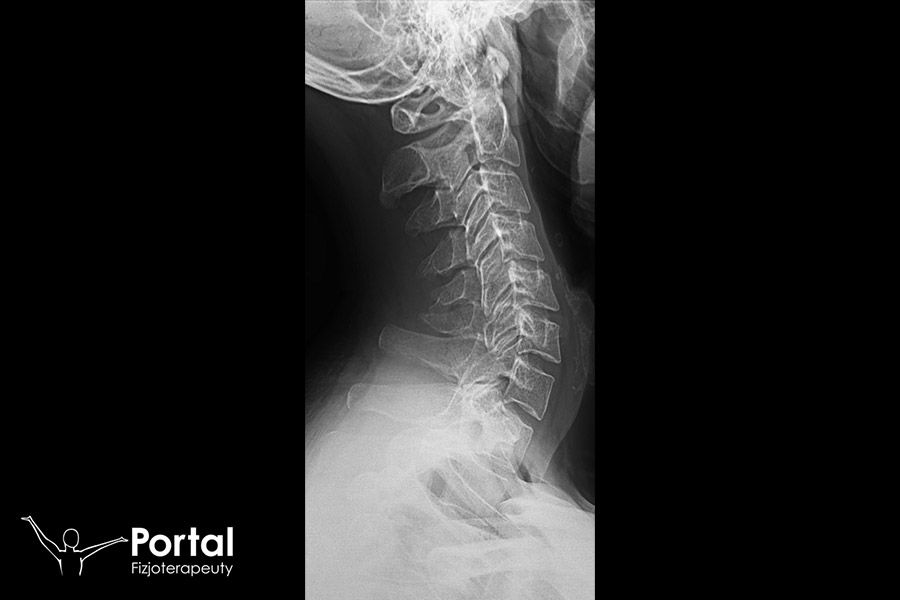

Odprostowanie lordozy szyjnej określane jest również jako jej zniesienie. To bardzo częsty problem XXI wieku, na co w dużej mierze